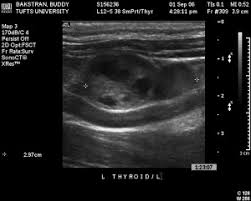

Thyroid Cancer In Dogs Petcure Oncology from petcureoncology.com I am wondering how your dogs did/doing? Cancer research uk said using dogs would be impractical, but discovering the chemicals the dogs can smell could lead to new tests. Sue is most passionate about raising cancer awareness & has developed see something, do aspirate.® to promote early cancer detection and diagnosis. Most service a local area, but some will bring a. Most thyroid gland tumors do not affect thyroid hormone levels. Some people testify by their own experiences that yes, it has been done and it has saved their lives. Dozens of therapy dog organizations across america offer visits. Cancers result from accumulation of mutations over y.

Kelsey Thyroid Cancer Survivor Yale Cancer Center from ysm-res.cloudinary.com The lifespan of a dog with malignant cancer is not predictable. Just how can they do it? Can i wash duffel bag in the washing machine. He's got cancer of the spleen, liver and pancreas. Your vet can determine through an examination that the thyroid is enlarged. Whereas we used to expect our pets to die of renal or. I don't have a thyroid anymore. Having cancer was in no way easy, but my life was starting to become more positive because of it.